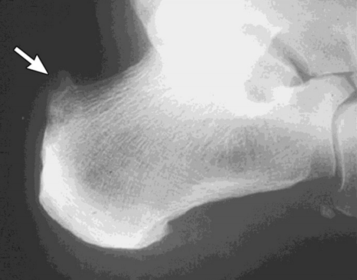

What disease is this? What does the arrow indicate? | Rheumatoid arthritis. Arrow = Bone erosion secondary to inflammation of retrocalcaneal bursa. |